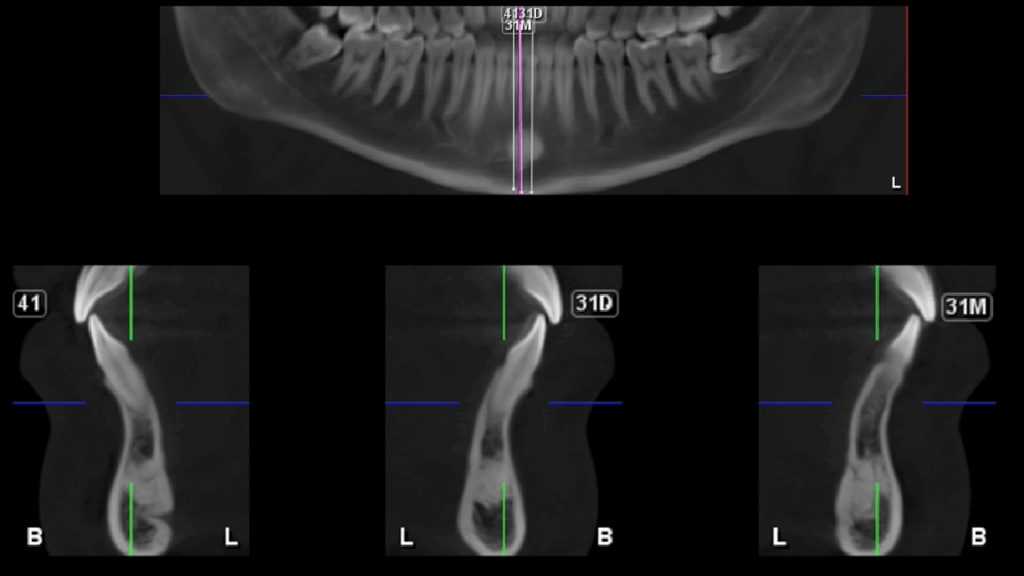

En la radiografía panorámica (Figura 1), se aprecia imagen radiopaca proyectada sobre sínfisis mandibular.

Radiografia Panorámica